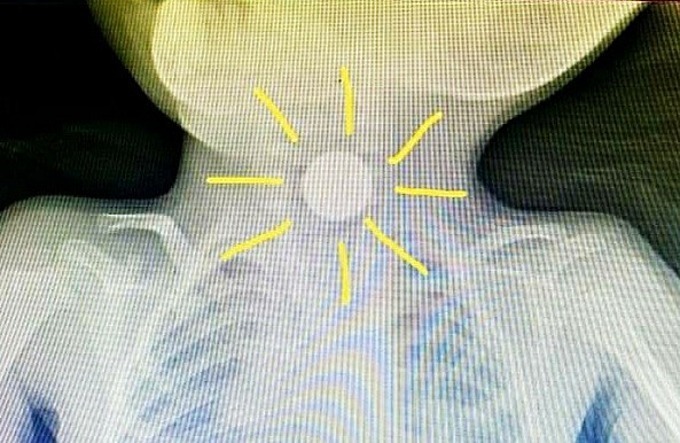

Bác sĩ Lê Đức Lộc cùng ê kíp đã khẩn cấp nội soi đêm 25/9, gắp viên pin đang kẹt ngay cơ thắt thực quản trên. Dị vật khá to, bác sĩ tưởng nhầm là đồng xu khi mới xem phim X-quang. Viên pin khiến bé liên tục nhợn ói.

Hình ảnh viên pin trên phim X quang. Ảnh: Bệnh viện cung cấp.